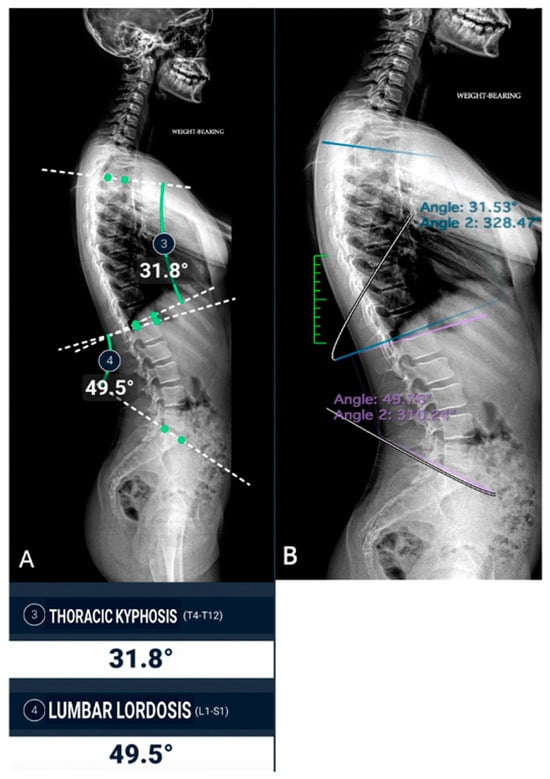

All images were acquired using the same digital radiography scanner (Bloomix 120 ED-R, Trade Art Manifacturing, Via della Pisana 1353, 00163 Rome, Italy) with patients in a standing weight-bearing position, in order to reproduce physiological load conditions on the spine. For each patient, both anteroposterior (AP) and lateral projections were obtained, covering the entire spine from the second cervical vertebra (C2) to the last sacral vertebral body (S5), including the pelvic bones and both femoral heads to allow evaluation of spinopelvic parameters. The dedicated scanner used in this study enables the acquisition of the entire spine in a single exposure, without the need for image stitching, thus reducing potential misalignment artifacts and ensuring greater measurement accuracy. Standardized positioning protocols were adopted to minimize patient rotation and to maintain consistent image quality across all examinations. All acquisitions were performed by experienced radiographers according to the department’s routine protocol for whole-spine evaluation. Exposure parameters, such as tube voltage and current, were adjusted based on patient size and age to optimize image quality while maintaining the radiation dose as low as reasonably achievable (ALARA principle) (Figure 1).

Figure 1. Full-spine radiographs were acquired in standing position using the same dedicated scanner (Bloomix 120 ED-R). (A) Anteroposterior (AP) view; (B) lateral view. For each patient, AP and lateral projections were obtained from the base of the skull to the last sacral segment, including the hip bones and femoral heads. The scanner enabled the acquisition of the entire spine in a single shot, without the need for image stitching.